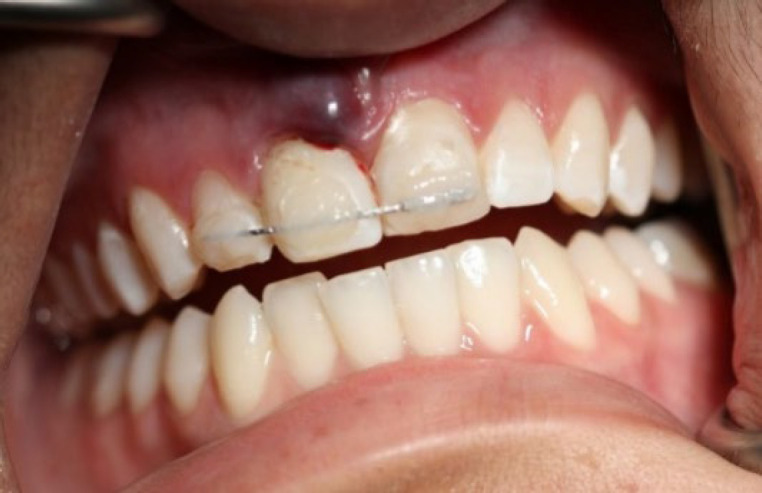

急性根尖脓肿(AAA)是一种以自发疼痛、脓形成和肿胀为特征的快速发作的炎症性疾病,通常由牙髓坏死引起。并发症可能包括全身性表现和严重的后果,如牙齿挤压。本病例报告描述了一例罕见的AAA引起上颌中切牙快速挤压的17岁女性病例。患者表现为自发的疼痛和牙齿的活动,并伴有局部肿胀。临床和影像学评估显示牙髓坏死、AAA级和根尖骨稀疏。紧急治疗开始了,包括用氢氧化钙进行管内药物治疗和暂时的牙齿夹板。随后的治疗包括用杜仲胶和密封剂进行封闭,然后进行永久性修复。5年的影像学和临床资料显示根尖周围完全愈合,牙齿活动正常,无症状复发。有效的管理,包括及时的根管治疗和夹板,导致了成功的长期结果。该病例强调了及时诊断和及时定制治疗的重要性,以管理AAA和预防严重并发症。

An acute apical abscess (AAA) is a rapid-onset inflammatory condition characterized by spontaneous pain, pus formation, and swelling, often resulting from pulp necrosis. Complications may include systemic manifestations and severe outcomes, such as tooth extrusion. This case report describes a rare instance of AAA causing rapid extrusion of a maxillary central incisor in a 17-year-old female. The patient presented with spontaneous pain and mobility of the extruded tooth, accompanied by localized swelling. Clinical and radiographic evaluations revealed pulp necrosis, an AAA, and apical bone rarefaction. Emergency treatment was initiated, including intracanal medication with calcium hydroxide and temporary splinting of the tooth. Subsequent treatment involved obturation with gutta-percha and sealer, followed by permanent restoration. Radiographic and clinical recalls up to 5 years demonstrated complete periapical healing, normal tooth mobility, and no recurrence of symptoms. Effective management, including timely root canal therapy and splinting, led to successful long-term outcomes. This case underscores the importance of prompt diagnosis and immediate, tailored treatment to manage AAA and prevent severe complications.